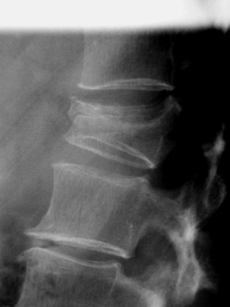

腰椎圧迫骨折

正常な背骨

圧迫骨折をした背骨

X線(レントゲン)検査を行うことで確定します。